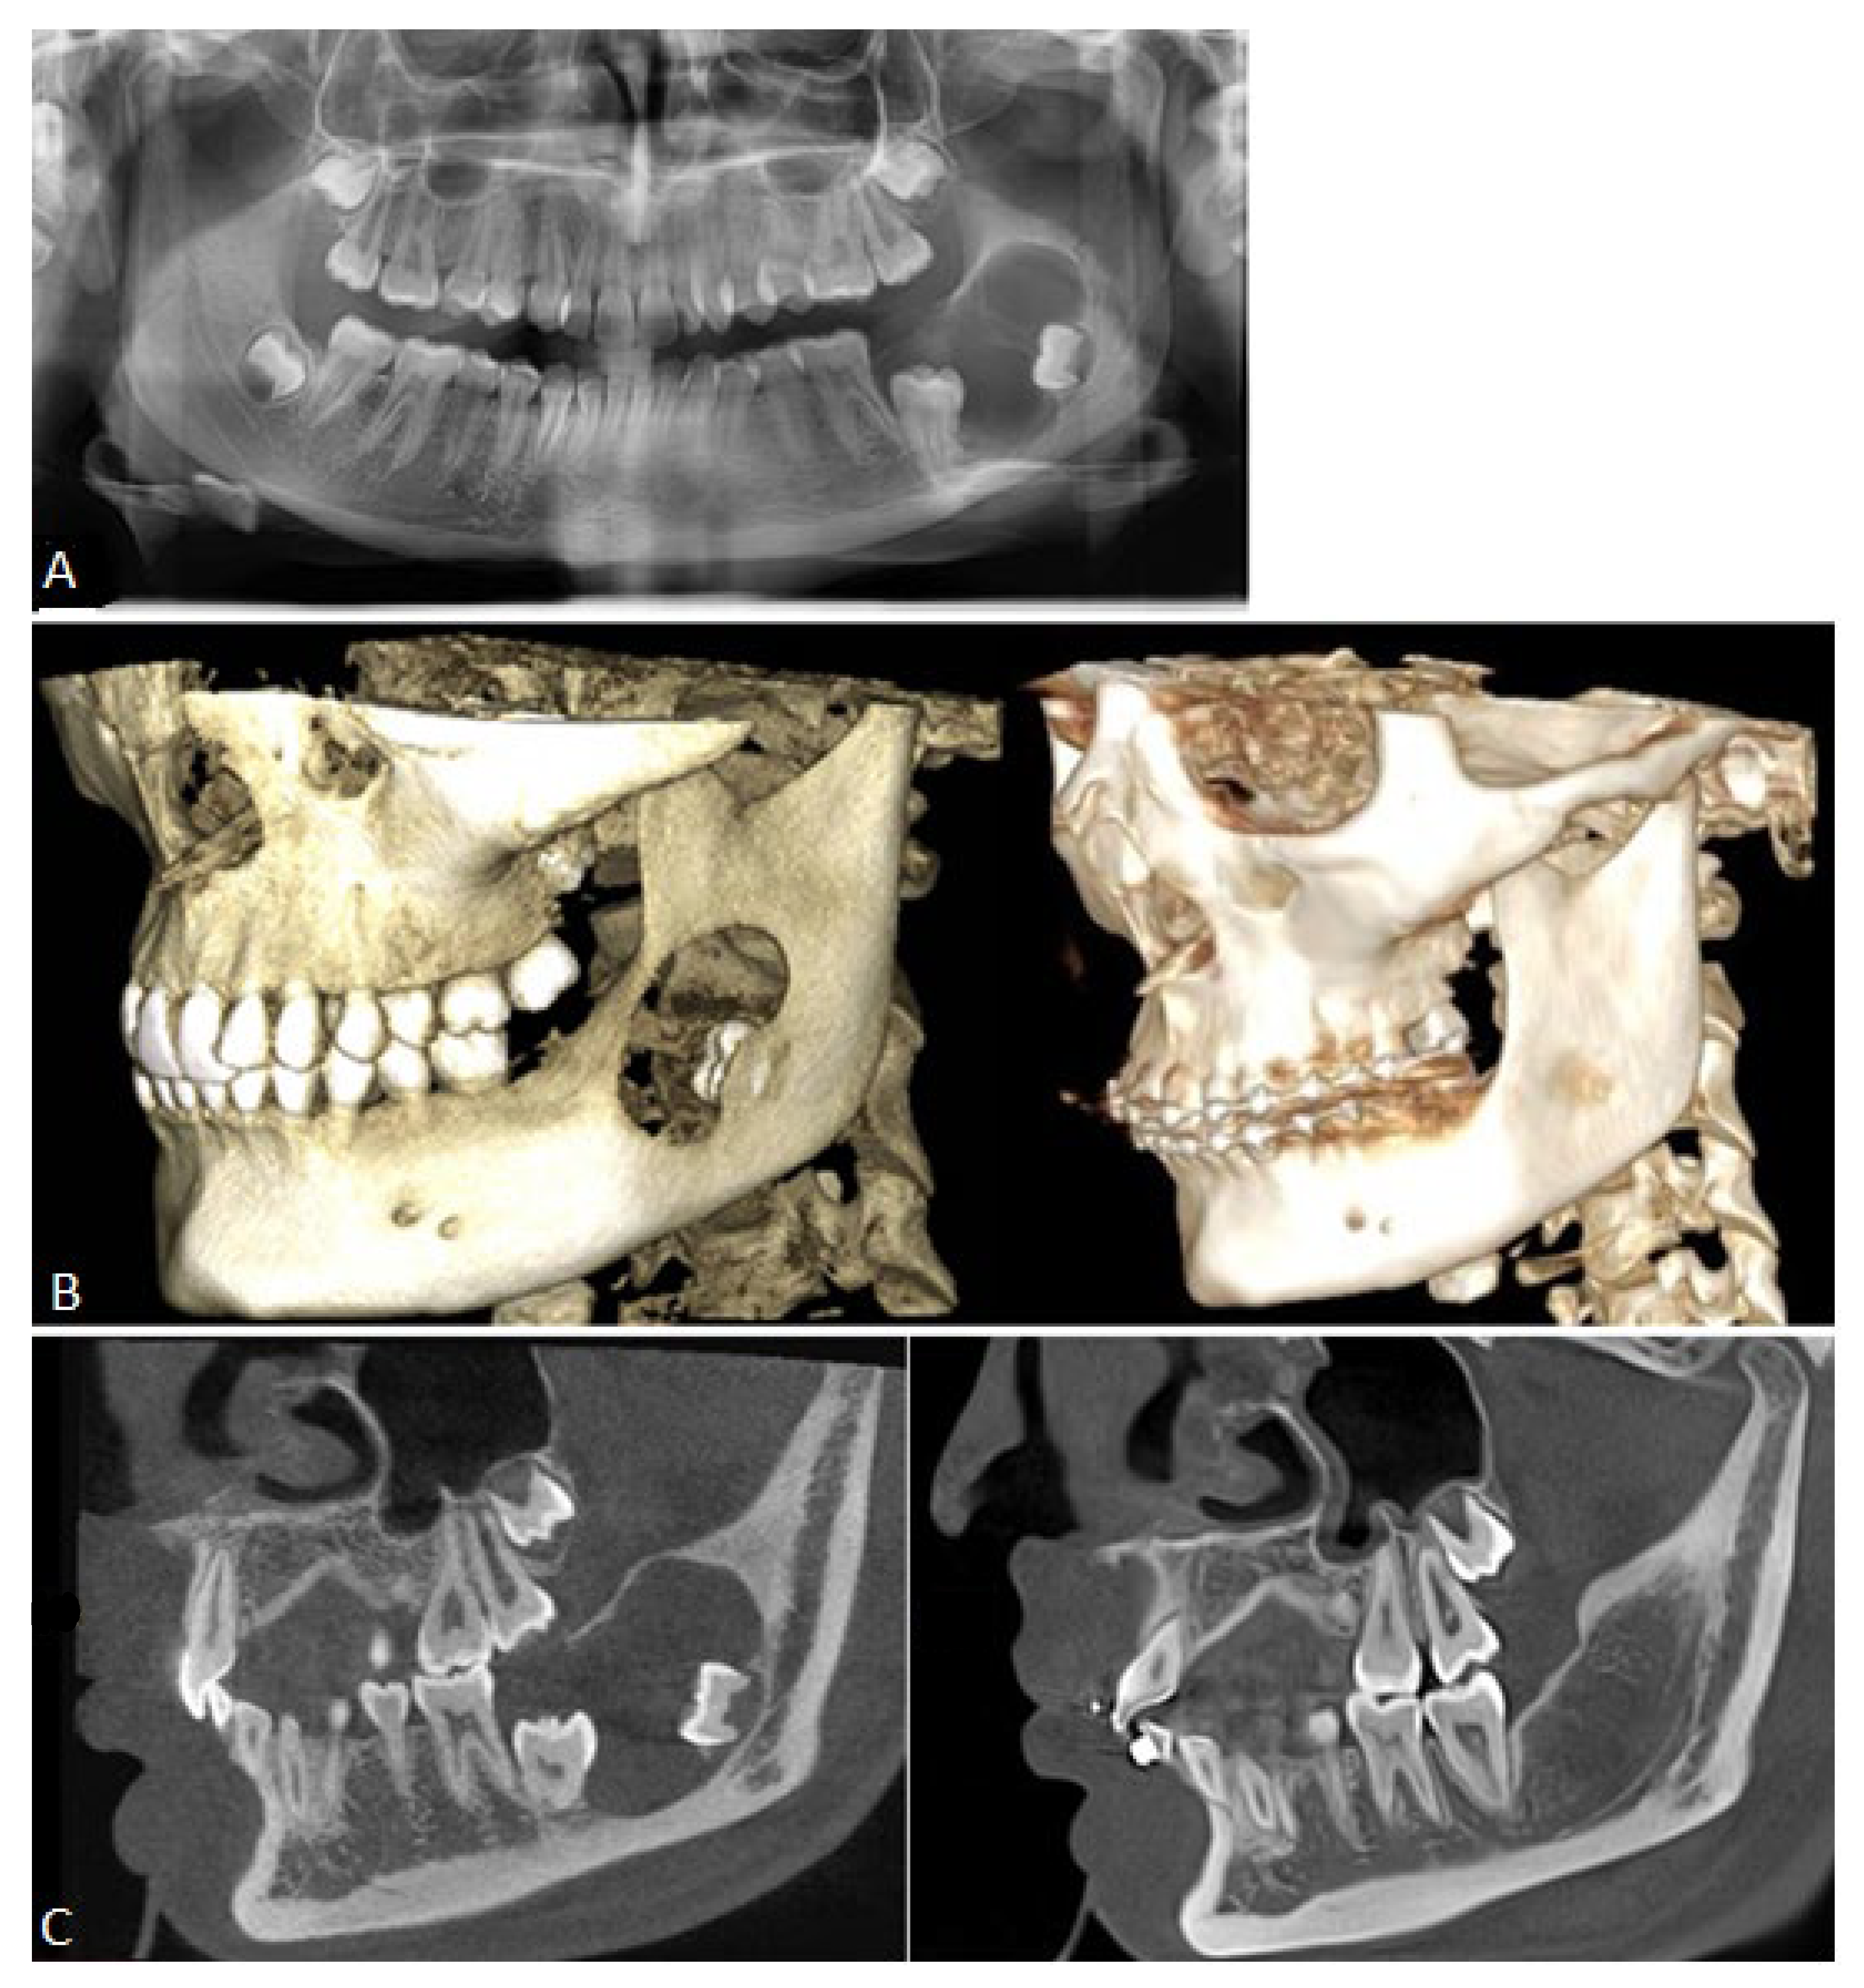

2. Case Presentation